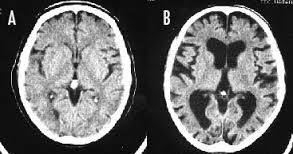

>>4472 >>4473 喫煙するとBの脳みそになって こういう発言をするようになるというよい例だな 認知症が進んで判断力が狂ってる